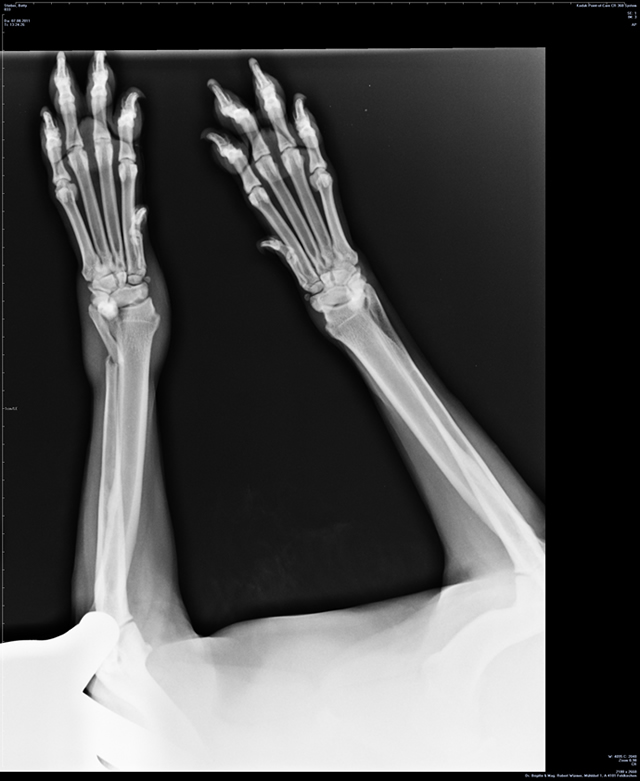

Röntgendiagnostik / Ultraschall

Unsere moderne Röntgenanlage ermöglicht die Aufnahme von Röntgenbildern auf höchstem Niveau.

- HD/ED Röntgen: zugelassen für SVÖ und Hirtenhunde, ÖKV